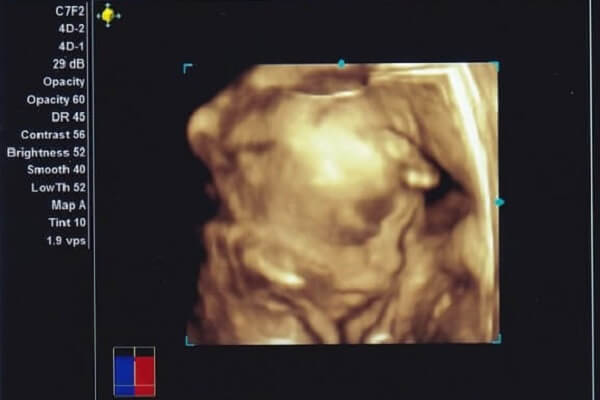

3Dエコーはその名の通り、3次元(長さ・幅・奥行き)の超音波で、赤ちゃんの立体的な写真(静止画)を撮ることができます。

4Dエコーとは、3Dに「時間」の概念を加え、4次元にしたもの。3Dエコーでは静止画しか見られないのに対し、赤ちゃんのしぐさや表情といった動きを動画で見ることができます。

赤ちゃんの外見を立体的にみられるので、外見上のトラブルがないかを調べることができるというメリットがあります。

ただし、赤ちゃんの向きによっては鮮明な画像を見ることができない場合もありますし、視野にも限界がありますので、全てのトラブルを必ず検知できるわけではありません。

また、見られるのは体表面のみなので、内臓のトラブルを探す際や、骨の発育状況を調べる際などには従来の2Dエコーが向いています。